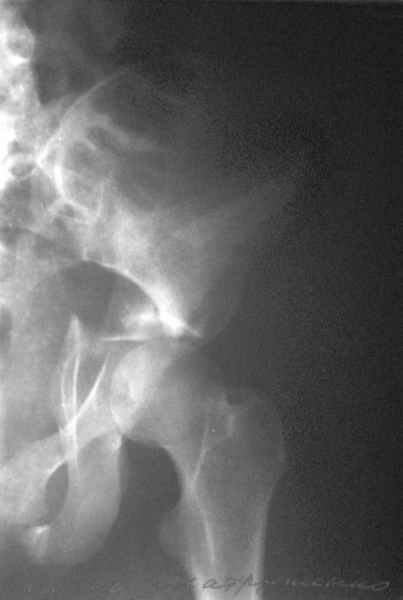

Посылаю схемы и 3D реконструкцию подобного повреждения. Называется он полным высоким двухколонным переломом вертлужной впадины, а "переломы крыла и тела подвздошной кости" входят в это понятие.

Вариантов остеосинтеза много (можно и не оперировть, т.к. конгруентность при таких переломах как правило сохраняется)

1 закрытая репозиция аппаратом + фиксация через проколы винтами

2 закрытая репозиция передней колонны + открытая задней колонны из задне-неружного доступа

3 открытая репозиция передней колонны из подвздошнго доступа + открытая задней колонны из задне-наружного доступа

4 открытая репозиция из илиоингвинального доступа

5 открытая репозиция из Y образного доступа

Я бы ориентировался на Y образный доступ

или из двух если есть сомнения в целостности задних отделов крыла.

прикладываю схему доступа и случай.

Одним задне наружным переднюю колонну не достать, а илио-ингвинальный более сложный не позволяет контролировать суставную поверхность и трудно управлять задней колонной.